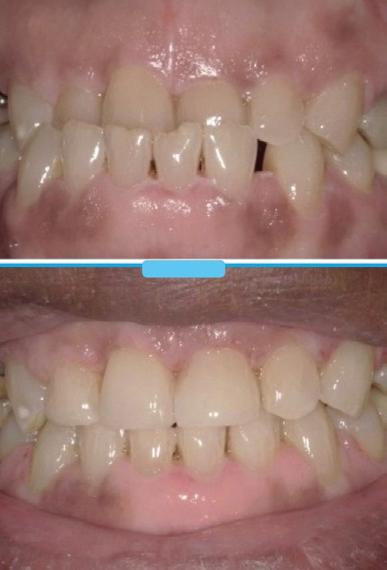

Submitted By Sivakumar Sreenivasan, DMD, MDS Dental Implant Center of Rockville

Can just four implants replace all of the teeth on the top or the bottom of your mouth? Thanks to advances in dental implant technology, that answer is a resounding yes.

Tooth loss is extremely common among adults, especially as we age. Rather than living with the discomfort and hassles of dentures, many people are opting for what is called “all-onfour” dental implant restoration.

An implant is a small titanium

screw that fits inside your jawbone and replaces the root-part of a missing tooth. Minor surgery is required to insert the implants. Once the implant is in place, a crown is attached to give you a highly realistic-looking and functional prosthetic tooth.

You do not need a dental implant for each and every one of your missing teeth. All you need is four precisely placed implants on the top of your mouth, and four on the bottom, to restore your full smile. That’s the beauty of the all-on-four. And because the implant is made of titanium, it has the unique ability to fuse to living bone and function as part of it. So eventually, the dental implant becomes part of the jawbone and serves as a strong, longlasting foundation for your new teeth.

Besides ensuring that your implants are permanently fixed in place, this bone fusion has another important benefit: it prevents future bone loss in the jaw. This helps to maintain a more youthful facial structure – and better